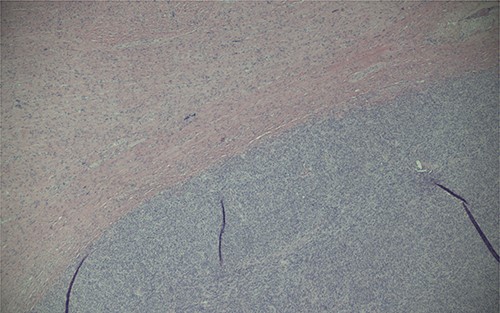

Magnification (40x) of histologic section of prostate, showing STUMP (upper left of image) and adjacent sarcoma (lower right of image).